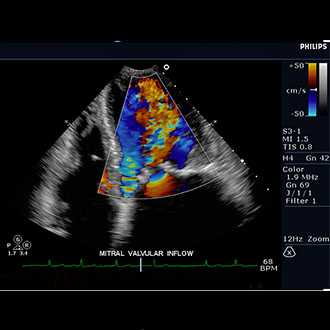

Doppler ultrasound is a special ultrasound technique that evaluates blood as it flows through a blood vessel, including the body's major arteries and veins in the abdomen, arms, legs and neck.

In an ultrasound examination, a transducer both sends the sound waves into the body and receives the echoing waves. ... Doppler ultrasound, a special application of ultrasound, measures the direction and speed of blood cells as they move through vessels.